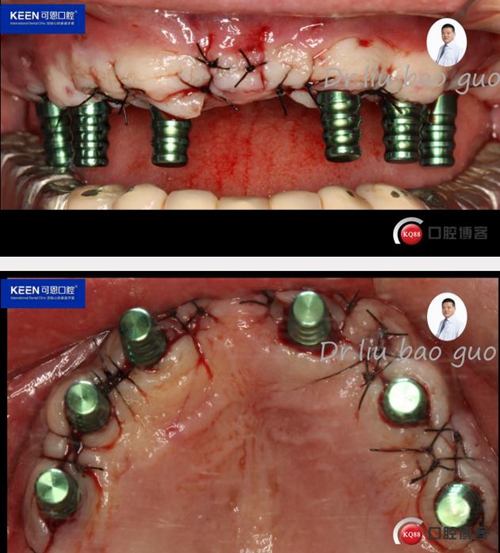

手術過程

10.jpg

11.jpg

(因設備限制,未能實現手術全程數字化導板,僅在手術之前導板定位)